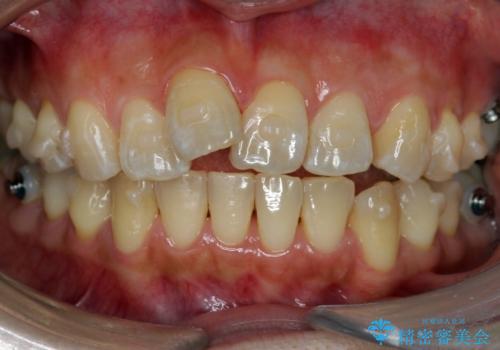

- インビザライン

- 1年11ヶ月

上の奥歯を後ろに下げて治療をしました。

矯正用のミニスクリューを使用しています。

上の前歯もIPR(エナメル質をわずかに削る処置)を行っています。